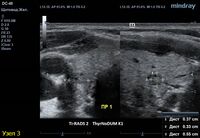

2) Узел у перешейка, не прорастает капсулу щитовидной железы (0 баллов), больше широкий чем высокий (0 баллов), не имеет кальцинатов (0 баллов), с ровным четким контуром (0 баллов), гипоэхогенный (2 балла), тканевой структуры (2 балла). Количество баллов 4, ACRTi-RADS4, ThyrNoDUMК6. Пункция не показана в связи с малым диаметром узла (более 1,5 см для Ti-RADS4), рекомендовано наблюдение.